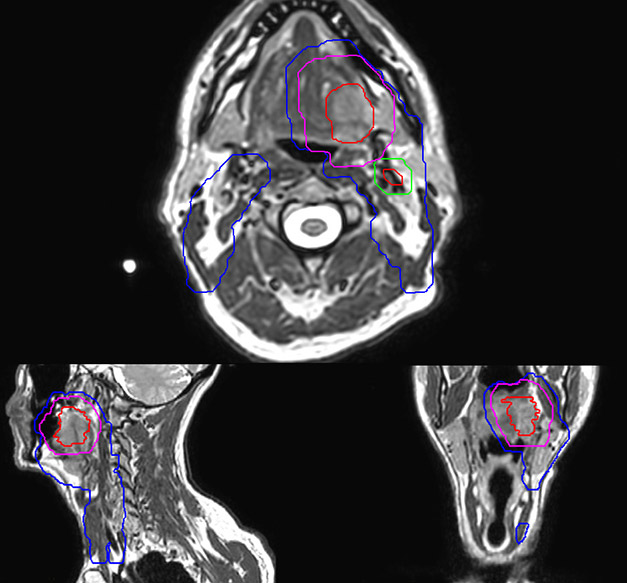

Epidermoid carcinoma of the left tongue base

The patient was diagnosed with an epidermoid carcinoma of the base of the left invading the amygdala lodge and the amygdaloglossal groove. Radiochemotherapy with curative aim was prescribed with a dose of 70 Gy for the tumor, 66 Gy on the suspicious nodes and 56 Gy on the elective drainage areas - in 33 fractions.

Comparison of CT simulation scan (left) and T2W 3D MRI (right)

MR-based target contouring on 3D T2W TSE in transversal, sagittal and coronal planes.

Personalized VMAT dose planned in Philips Pinnacle.